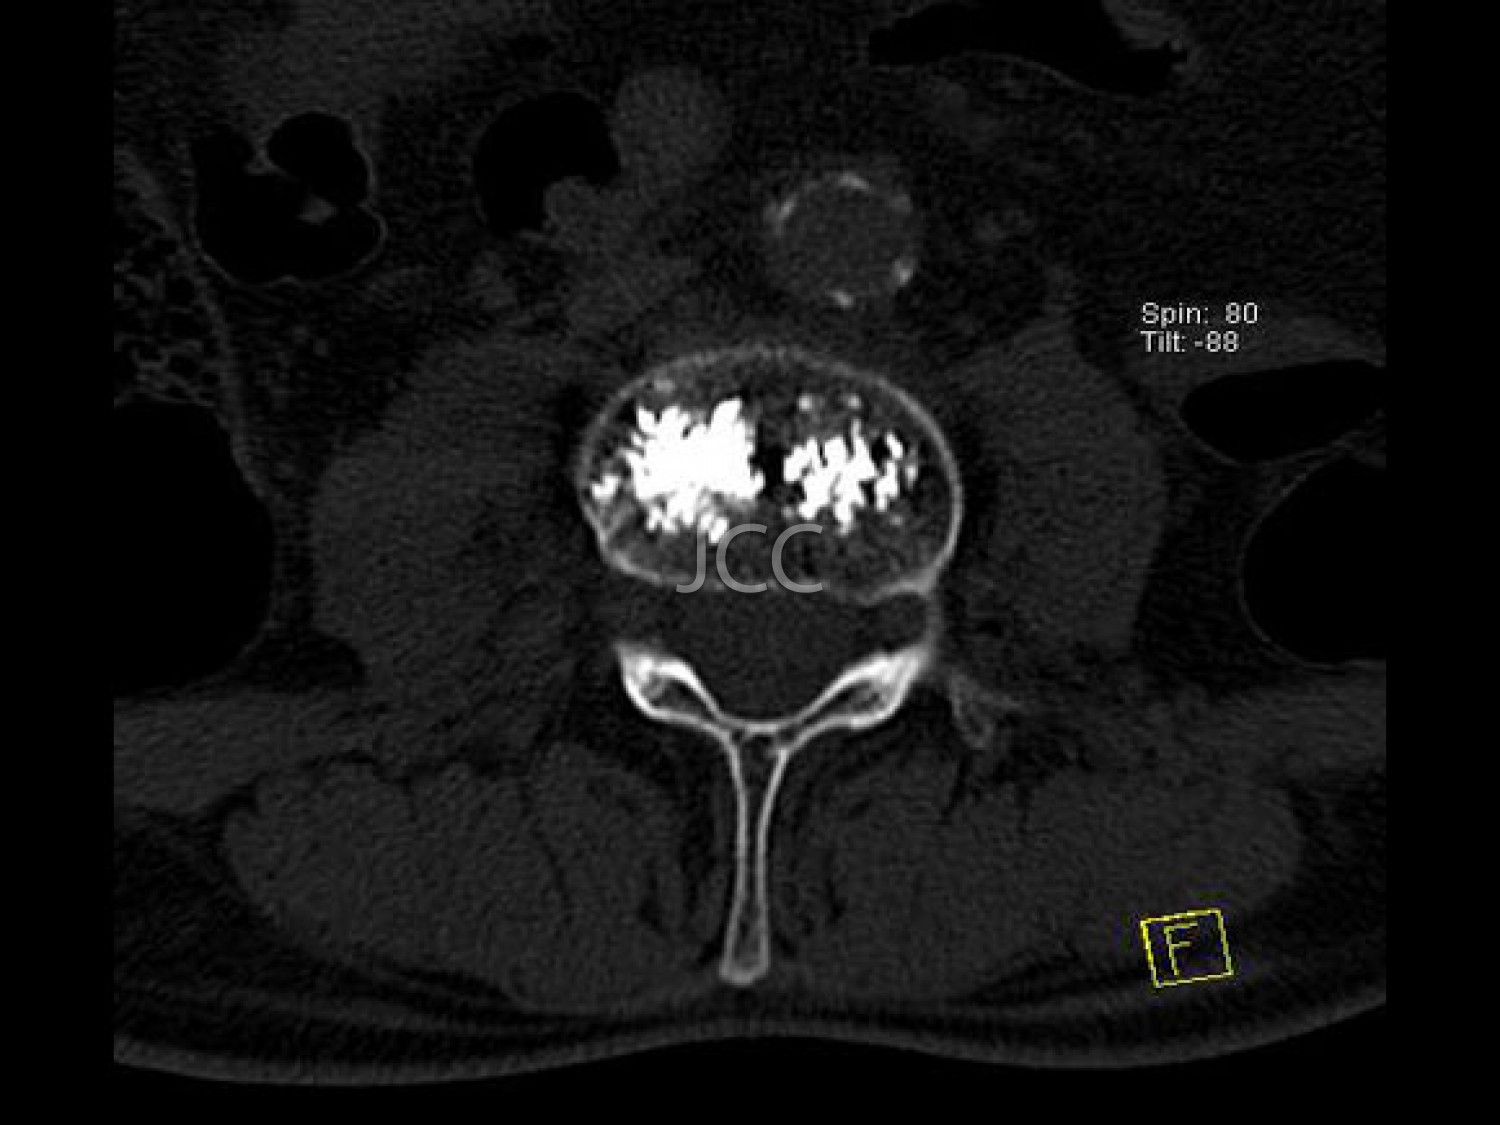

Vertebroplastia